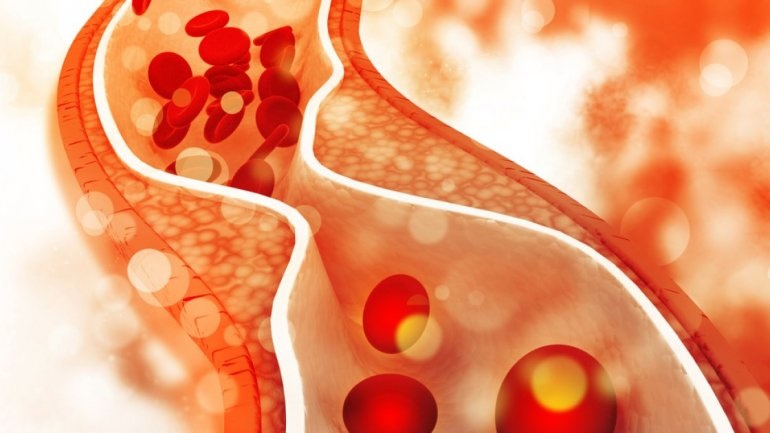

Κινήσου ενάντια στη θρόμβωση

Το μήνυμα «Κινήσου ενάντια στη θρόμβωση» ήταν το κεντρικό μήνυμα όλων των ομιλητών κατά τη διάρκεια Συνέντευξης Τύπου που οργάνωσε το Ι.Μ.Ε.Θ.Α., με αφορμή τον εορτασμό της Παγκόσμιας Ημέρας Θρόμβωσης (13 Οκτωβρίου). Ο εορτασμός της Παγκόσμιας Ημέρας Θρόμβωσης που φέτος κλείνει τα 10 χρόνια, έχει την επιστημονική αρωγή 19 Επιστημονικών Εταιρειών που σχετίζονται με τη […]